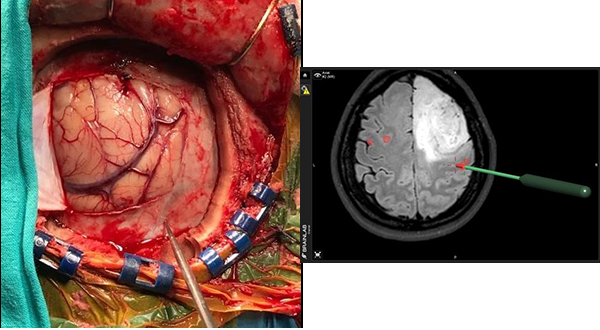

Se incluyeron 48 pacientes portadores de tumores intra axiales (Nº 25) y extraaxiales (Nº23) próximas al área motora, con capacidad de realizar la tarea funcional motora por RMf, y que fueron sometidos a cirugía con ECD. Durante la cirugía se realizaron 220 registros de ECD en total de la población de pacientes estudiados.

Se incluyeron 48 pacientes portadores de lesiones expansivas intra axiales (Nº 25) y extraaxiales (Nº23) adyacentes ó próximas al área motora, independientemente del tamaño y la naturaleza de la lesión. Durante la cirugía se realizaron 220 registros de ECD en el total de la población de pacientes estudiados.

La cirugía se inicia, realizando en la estación de trabajo del navegador Brain Lab Vector Vision II la fusión de imágenes pre quirúrgicas establecidas en el protocolo de neuronavegación antes mencionado por un procedimiento de fusión automática. La secuencia funcional BOLD se fusiona de manera manual, ajustando el tiempo que duran las tareas motoras y los períodos de descanso.

Con ayuda de la herramienta de corte se planifica una craneotomía ajustada al criterio de abordaje mínimamente invasivo que exponga los límites del tumor y el área funcional motora indicada por la RMf.

- Monitoreo Neurofisiológico Intraoperatprio

Realizado el colgajo dural el primer paso es la identificación del surco central por sus características morfológicas en la secuencia T1 de la RMN. Luego se procede a corroborar la funcionalidad cortical pre y post central de la corteza anatómica observada en la RMN, con ayuda de un electrodo de cuatro polos para verificar la inversión de fase de la onda de respuesta N20 en un registro de Potencial Evocado Somato-Sensitivo por estimulación eléctrica del nervio mediano contralateral a la lesión, esto permite la localización neurofisiológica del surco central.

3º Colocación de etiquetas numeradas sobre la superficie cortical, y estimulación espacial cortical directa (ECD)

El tercer paso del monitoreo intraoperatorio es la colocación de stickers numerados que nos permitan reconocer la relación espacial de la corteza quirúrgica con al área de activación de la RMfm. De esta manera se colocaron sobre la superficie cortical distribuyendo en forma aleatoria etiquetas estériles numeradas de 0.5 x 0.5 cm. separadas por una distancia aproximada de 1 cm. Las etiquetas cubrieron toda el área de la craneotomía incluyendo la corteza del tejido funcional registrado en la RMfm (expuesto en el abordaje) y la superficie cortical del tumor. Luego se procedió a la estimulación cortical directa (ECD) con estimulación bipolar con una corriente inicial de 4 mAmp, y si no se obtenían respuestas se incrementó sucesivamente a 8 y 12 mAmp. una frecuencia de 60 Hz y tres pulsos de 0.2 mseg de duración.